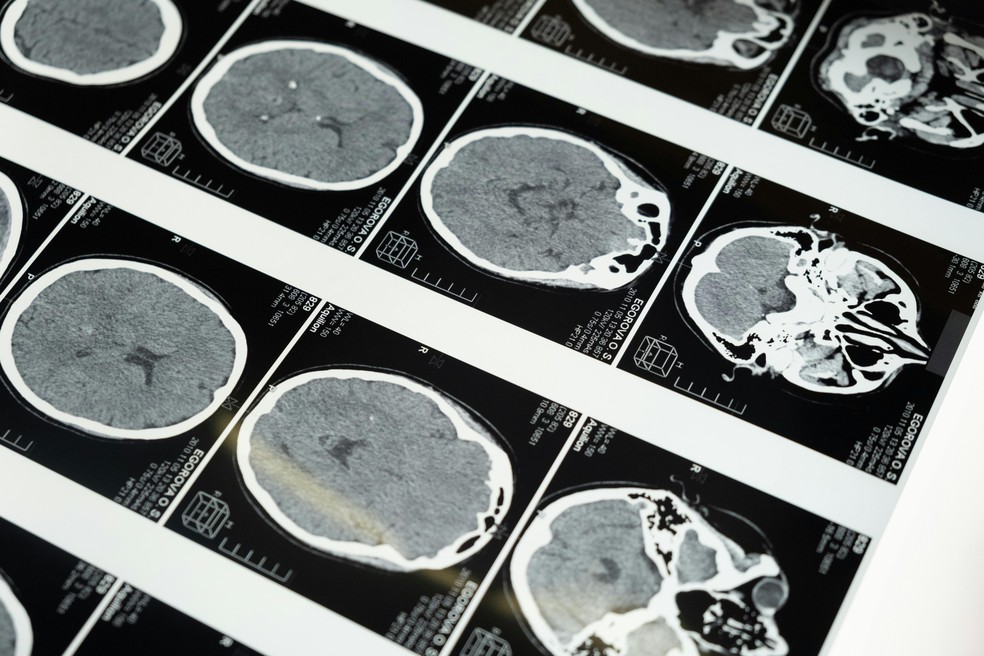

Exame de Imagem Cérebro — Foto: cottonbro studio via Pexels